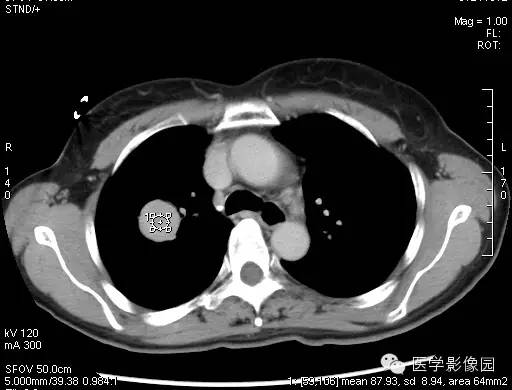

【病例】硬化性血管瘤1例CT影像表现

CT 平扫,肿块和软组织的密度很相似,单发性的PSH肿块形状为圆形 或类圆形,肿块的密度均匀,边缘也清晰可见。

动脉期的增强在中等以上,静脉期增强在动脉期的程度上有更深程度的强化,当肿瘤边缘不清晰时,就有呈现浅分叶、胸膜凹陷、短毛刺等现象,边缘清楚、光整,多数形态规则、少数可见浅分叶,无毛刺、空洞,无卫星灶,密度均匀,偶有钙化,无胸膜凹陷征。CT增强扫描显示病灶中等以上均匀或不均匀强化,且存在延迟强化现象,对PSH具有一定的诊断价值。